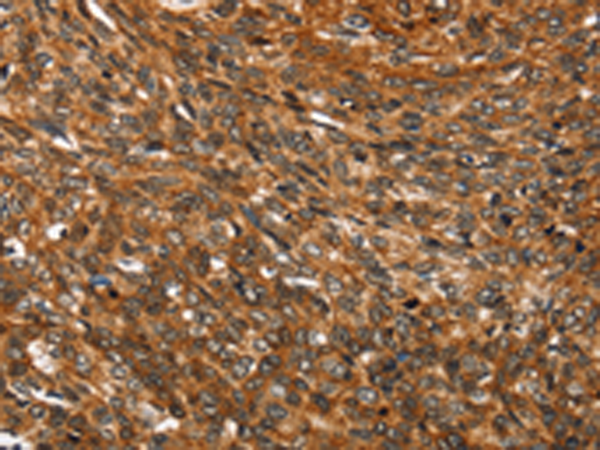

分类: 科研抗体货号: P08752别名: SEMAF; SEMAI; SEMACL1; M-SEMA-F应用: IHC反应种属: Human, Mouse